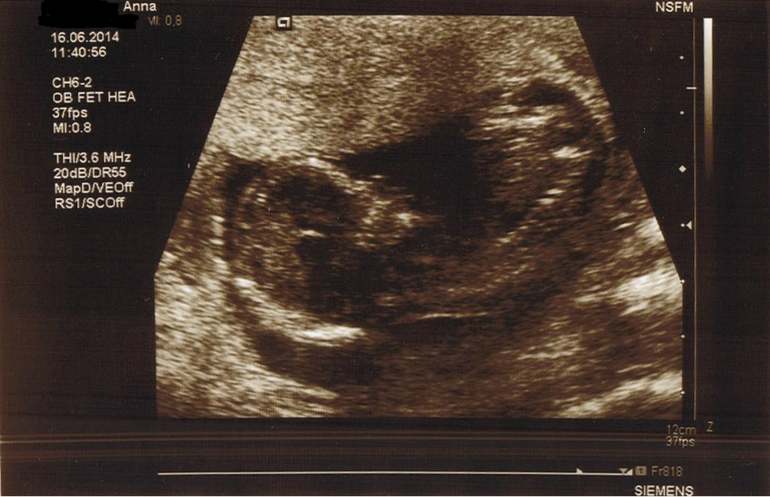

УЗИ в 12+6 нед / Дуо-тест

УЗИ, КТГ, доплерБыли в клинике Св. Олафа, что в Тронхейме, через пару дней после планового обследования. сайт клиники Делали дуо-тест на синдромы Дауна и Эдвардса, который мне полагается пройти по возрасту. Хотя и говорят, что делают его исключительно с 38 лет, но на тот момент мне было только 37 /в августе - 38/. Сделали УЗИ и сдала кровь. Через день позвонили из клиники и сказали, что отклонений нет и мне уже выслали письмо с результатами по почте.